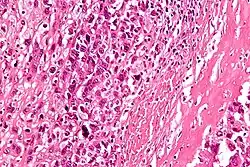

High-magnification micrograph showing osteoid formation in an osteosarcoma H&E stain

Microscopically: The characteristic feature of osteosarcoma is presence of osteoid (bone formation) within the tumor. Tumor cells are very pleomorphic (anaplastic), some are giant, numerous atypical mitoses. These cells produce osteoid describing irregular trabeculae (amorphous, eosinophilic/pink) with or without central calcification (hematoxylinophilic/blue, granular)—tumor bone. Tumor cells are included in the osteoid matrix. Depending on the features of the tumor cells present (whether they resemble bone cells, cartilage cells, or fibroblast cells), the tumor can be subclassified. Osteosarcomas may exhibit multinucleated osteoclast-like giant cells.[22]